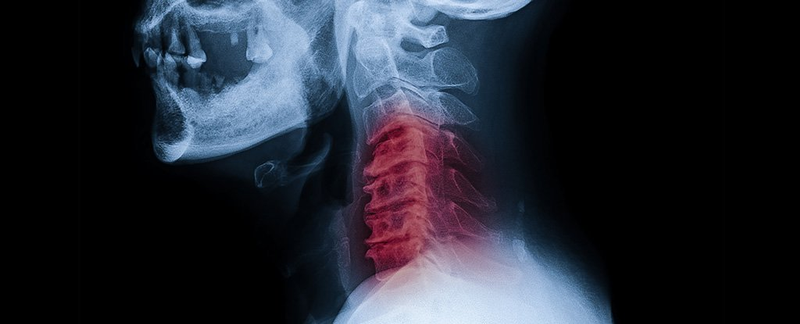

Al tronar su cuello desgarró su arteria vertebral, una de las arterias principales en el cuello que sube hacia el cerebro.

Un desgarro o disección de la arteria vertebral causa accidentes cerebrovasculares que pueden afectar a personas más jóvenes entre los 20 y los 30 años, y no tiene nada que ver con la salud de una persona.

Las arterias vertebrales en el cuello se unen en el cerebro para convertirse en la arteria basilar, que cumple el papel fundamental de suministrar sangre al tallo cerebral.